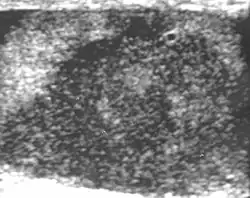

Embryonal cell carcinomas, a more aggressive tumor than seminoma usually occurs in men in their 30s. Although it is the second most common testicular tumor after seminoma, pure embryonal cell carcinoma is rare and constitutes only about 3 percent of the nonseminomatous germ cell tumors. Most of the cases occur in combination with other cell types. At ultrasound, embryonal cell carcinomas are predominantly hypoechoic lesions with ill-defined margins and an inhomogeneous echotexture. Echogenic foci due to hemorrhage, calcification, or fibrosis are commonly seen. Twenty percent of embryonal cell carcinomas have cystic components. The tumor may invade into the tunica albuginea resulting in contour distortion of the testis [Fig. 4].